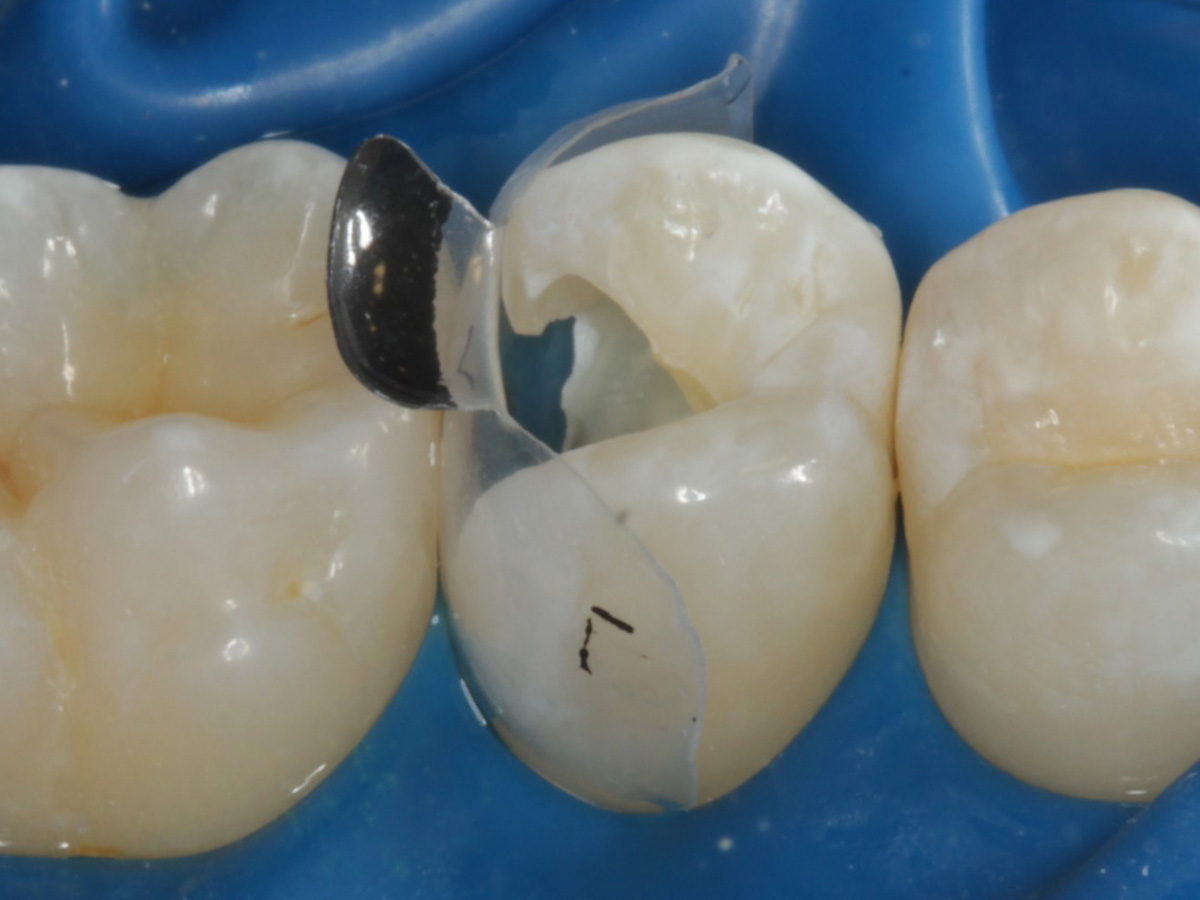

Abbildung 16

Nach Anbringung des Bioclear Twin Ring Universal und Lichthärtung des Einkomponentenadhäsivs

Abbildung 17

Starke Separation der Zähne durch hohe Spannkraft des Twinrings für strammen Kontaktpunkt

Abbildung 18

Bewusst kein Keil zur Vermeidung unerwünschter Matrizenverdrückung